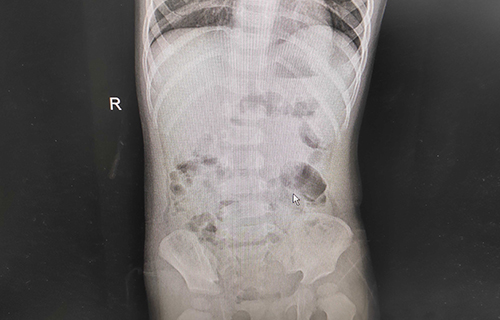

小米妈妈说,孩子发热整整1天,精神萎靡;呕吐2天,平均每天都得吐五六次,呈现非喷射状;腹泻3天,排便呈现水样、蛋花汤样便,尿少。家人急坏了,及时给孩子服用补液盐和双歧三联活菌(益生菌)。在a片网站 消化内科诊室内,小米依旧精神不振,并伴有轻度脱水。经查体,小米心肺无明显异常,腹部平软,肠鸣音活跃,神经系统正常。综合查体情况,医生初步诊断其为轮状病毒感染导致的小儿肠炎、轻度脱水。在进行肝功能、肾功能、心肌酶、血离子等检查后,医生发现小米的心肌酶数值异常,提示有心肌损害;血钾3.2mmol/L、血糖3.1mmol/L,均低于正常值。在对症治疗后,小米的临床症状得到极大缓解。